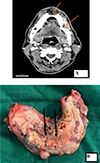

![]() |

Figure 2 (A) Radiology showing bony erosion of the mandible (marked by red arrows) and (B) gross image of the tumour of the same patient showing the ulceroproliferative tumour involving lower gingivobuccal sulcus (black arrows) and mandible. |